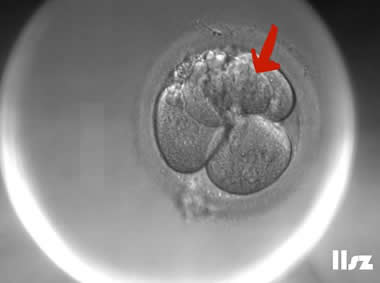

| |

逆向卵裂:在4细胞阶段,上方的2个细胞逆向卵裂,重新融合为1个细胞,4细胞变成了3细胞。 | |